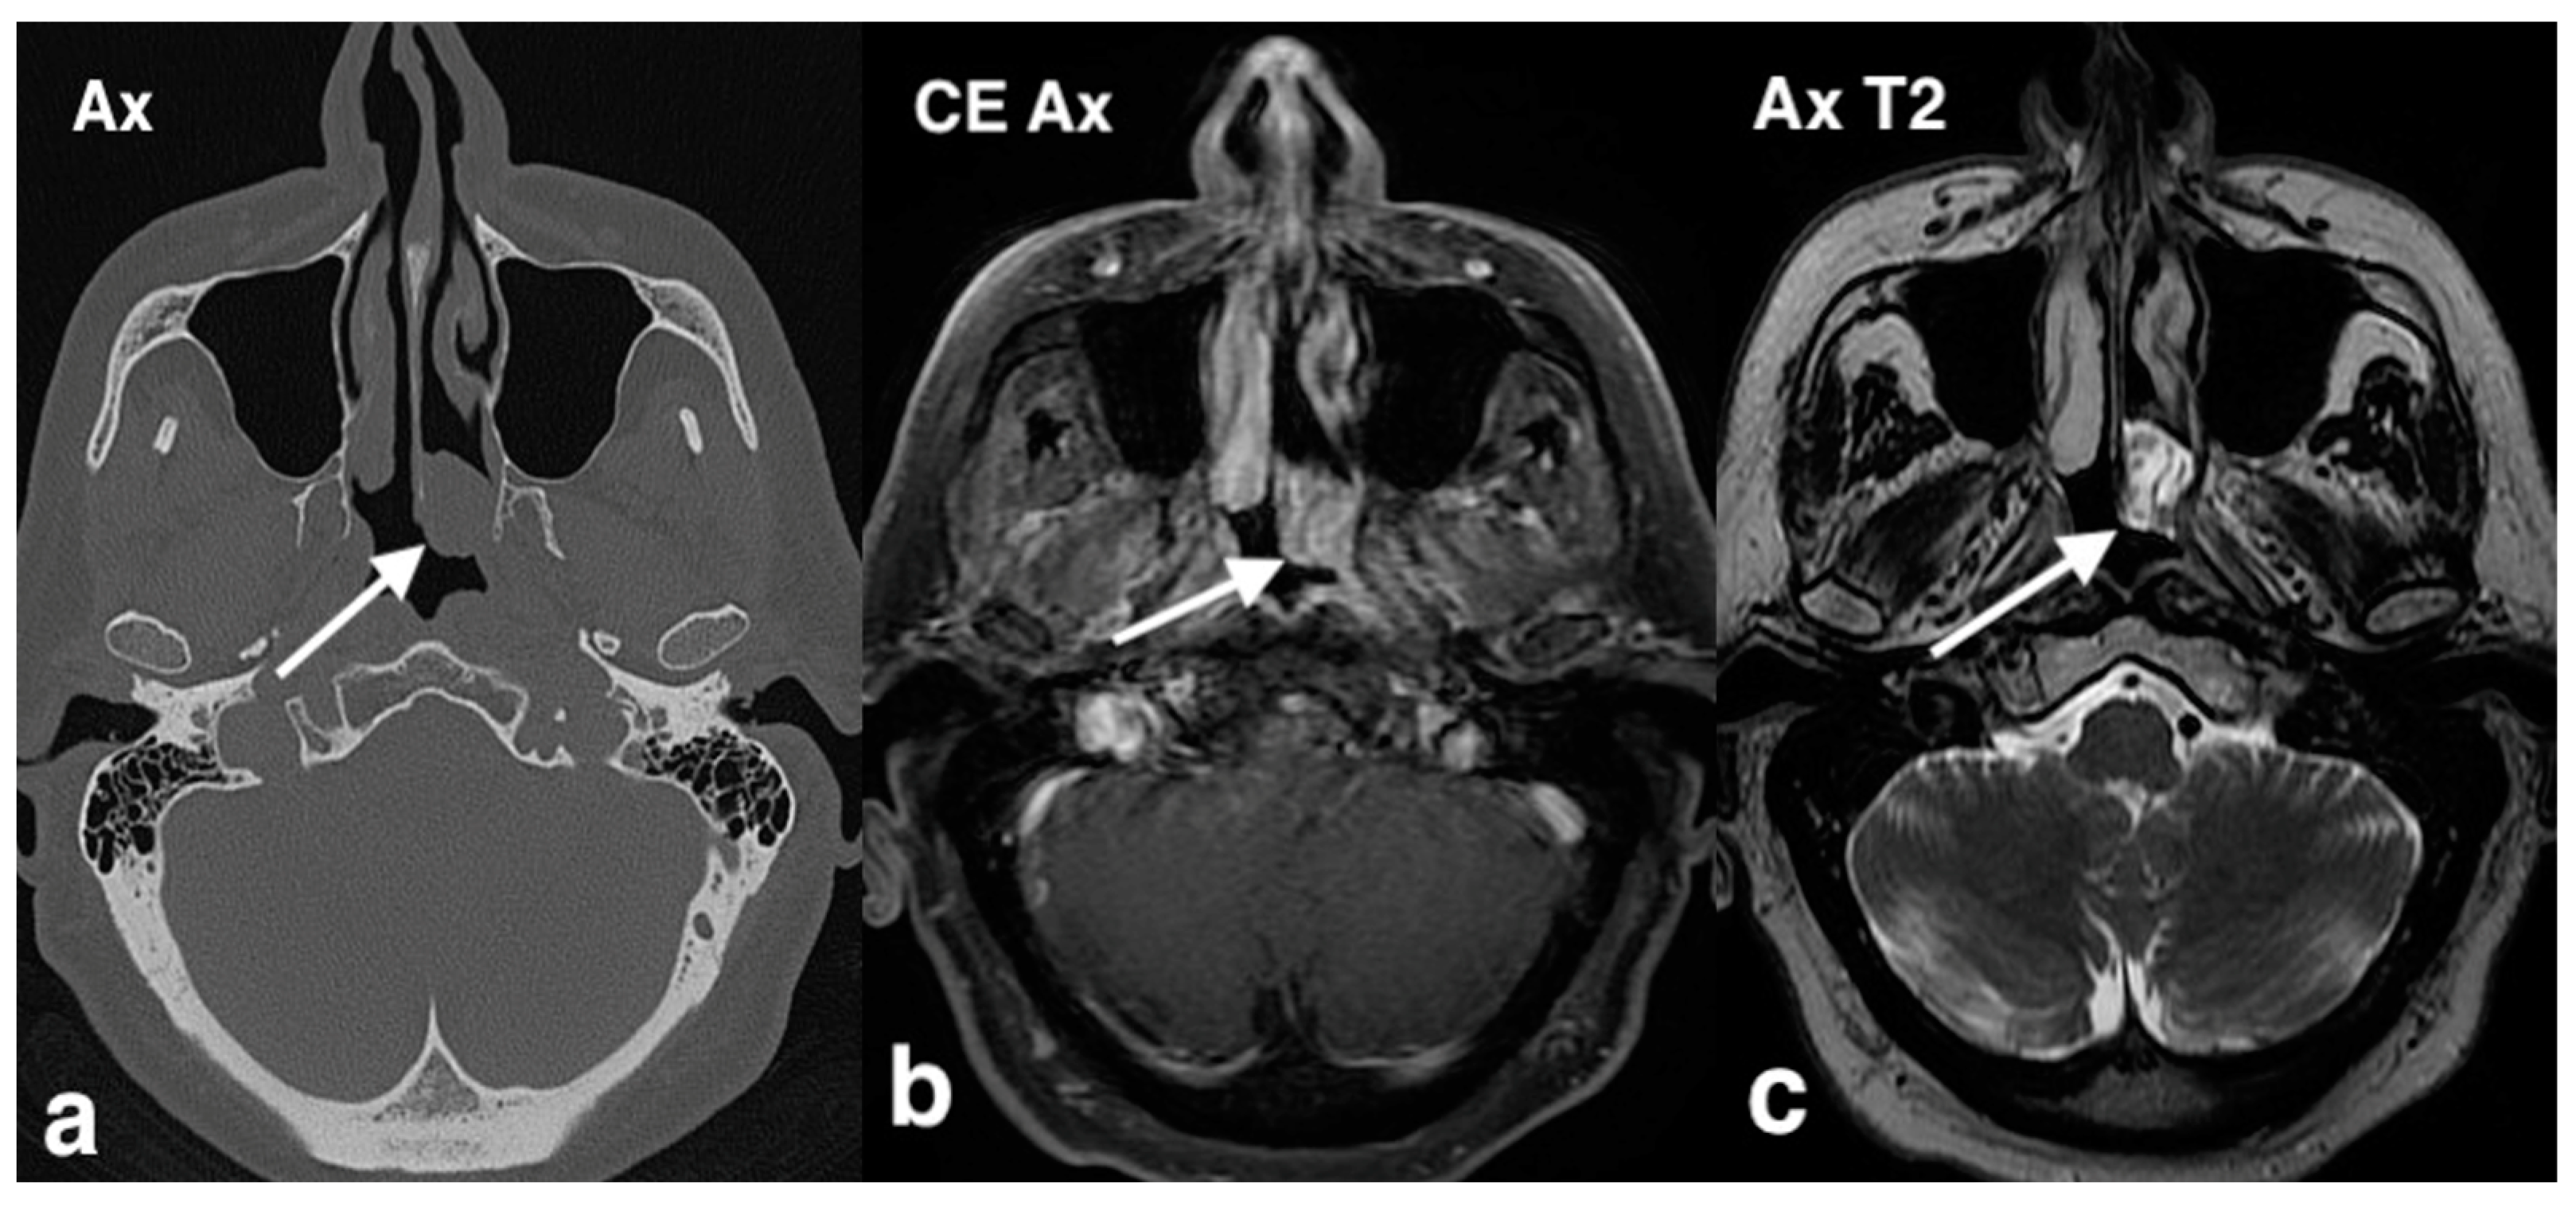

3.1.3. Inverted Mesiodens